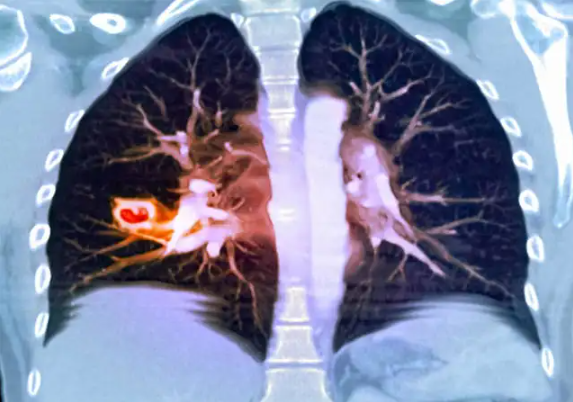

一名72岁男子来到医院进行体检。经询问,他连续咳嗽近半个月,并且有咳血的情况出现。CT显示他的左肺有一个7厘米大小的结节。病理检查为浸润性腺癌。而且仅仅一个月后复查,肿块以肉眼可见的速度进一步增大。在这种情况下,如果进行手术,大爷的身体能否承受的住还不一定。然而,如果肿瘤在没有手术的情况下继续发展,可能会发生淋巴转移。恐怕那时就没有转机之力了。

经过查询问诊记录,以及与病人家属沟通了解,大爷在六年前曾经做过一次CT检查。当时发现有一个0.8毫米的磨玻璃结节。医生有叮嘱过大爷定期回来复查,但大爷把这件事抛之脑后,这个无人看管的结节肆意生长,于是出现了如今的情况。